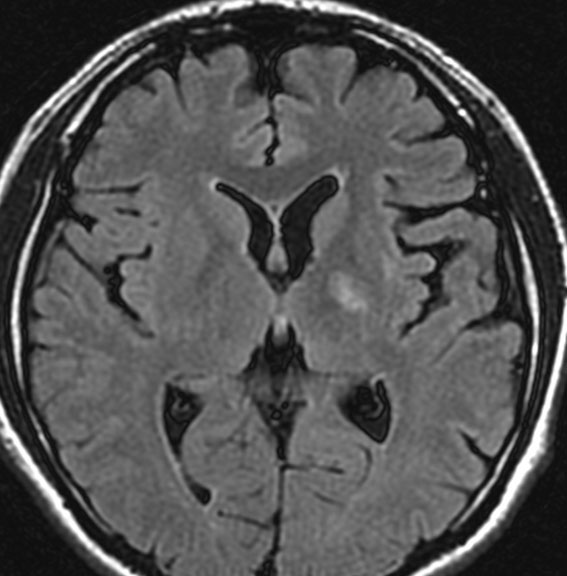

4回目のアバスチン投与後

アバスチンをどれだけ続ければいいのかははっきりしていません。2週間おきに6コースまでの投与が基本かもしれません。

この画像を見ると,放射線とテモダールの治療が有効であったのかなと思います。

注意,アバスチン投与を中断するとreboundで病変の急増悪が生じることがあります。